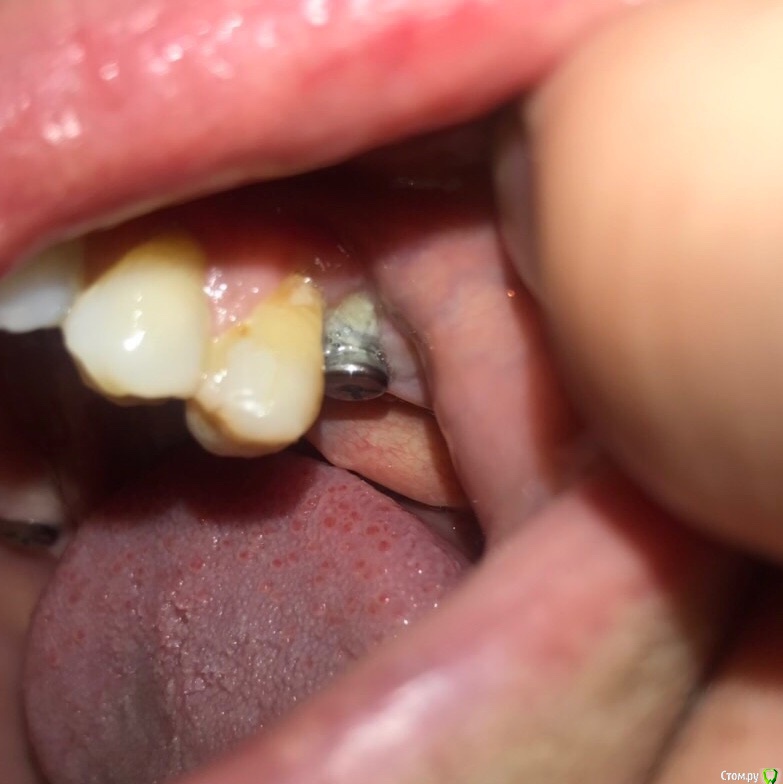

dr.Dre Опубликовано 28 ноября, 2018 Поделиться Опубликовано 28 ноября, 2018 Добрый вечер,коллеги было ли в вашей практике такое ,заглушка после 2 месяцев после имплантации оголилась ,2 недели как поставил формирователь и получил такой результат Ссылка на комментарий

Bier Опубликовано 5 декабря, 2018 Поделиться Опубликовано 5 декабря, 2018 фотка первая очень некачественная, это голая кость на имплантате? Ссылка на комментарий

Bier Опубликовано 5 декабря, 2018 Поделиться Опубликовано 5 декабря, 2018 мне думается, что вы выбрали слишком широкий диаметр и очень сильно недозаглубили имплантат. 3 Ссылка на комментарий

dr.Dre Опубликовано 6 декабря, 2018 Автор Поделиться Опубликовано 6 декабря, 2018 фотка первая очень некачественная, это голая кость на имплантате?да , извините за качество Ссылка на комментарий